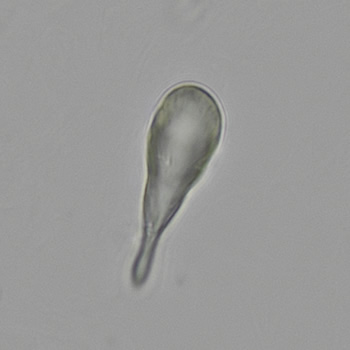

A very rare form involves a club-shaped morphology, with dimensions similar to those of erythrocytes. Remarkably, these crystals do not occur in isolation, but clump together to form characteristic rosette-like structures. The crystals are soluble in 30% hydrochloric acid, but insoluble in both 30% acetic acid and 10% potassium hydroxide.